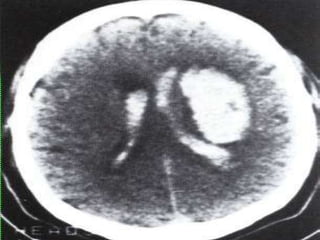

ESCALA DE FISHER: HALLAZGOS TOMOGRÁFICOS EN HSA Grupo  Descripción  1 No se detecta sangre 2 Depósito difuso o capa delgada de sangre cuando todas las capas verticales miden < 1mm de espesor 3 Coágulos localizados o capas verticales de sangre > 1 mm de espesor 4 Sangre subaracnoidea difusa o ausencia de sangre subaracnoidea pero con coágulo intraparenquimatoso o intraventrícular

ESCALA DE FISHER:HALLAZGOS TOMOGRÁFICOS EN HSA Grupo Descripción 1 No se detecta sangre 2 Depósito difuso o capa delgada de sangre cuando todas las capas verticales miden < 1mm de espesor 3 Coágulos localizados o capas verticales de sangre > 1 mm de espesor 4 Sangre subaracnoidea difusa o ausencia de sangre subaracnoidea pero con coágulo intraparenquimatoso o intraventrícular